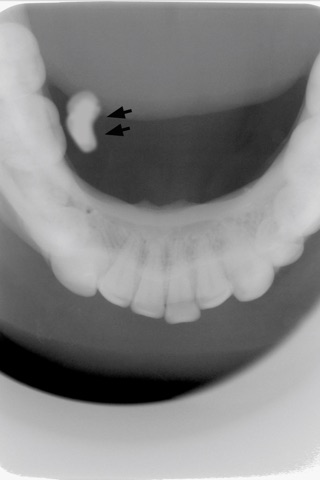

If so, this app will help you to judge, diagnose and practice from X-rays by bringing together all these real patient cases as a digital library.

Oral Radiology App is designed as a reliable learning tool for oral and maxillofacial radiology and created by the experts of the field. This data is tested and filtered several times. Perfectly simplified and clean information!